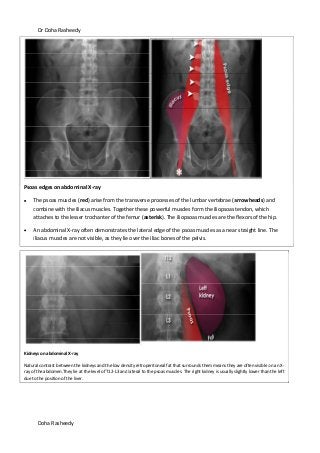

Psoas edges on abdominal X-ray

The psoas muscles (red) arise from the transverse processes of the lumbar vertebrae (arrowheads) and

combine with the iliacus muscles. Together these powerful muscles form the iliopsoas tendon, which

attaches to the lesser trochanter of the femur (asterisk). The iliopsoas muscles are the flexors of the hip.

An abdominal X-ray often demonstrates the lateral edge of the psoas muscles as a near straight line. The

iliacus muscles are not visible, as they lie over the iliac bones of the pelvis.

Kidneys on abdominal X-ray

Natural contrast between the kidneys and the low density retroperitoneal fat that surrounds them means they are often visible on an X-

ray of the abdomen.They lie at the level of T12-L3 and lateral to the psoas muscles. The right kidney is usually slightly lower than the left

due to the position of the liver.